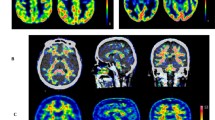

In addition to a temporal dissociation between clinical symptoms and amyloid there is a spatial dissociation between tau-related neurodegeneration and amyloid deposition (Fig. 2). Tau pathology begins in the medial temporal lobe and spreads outward to heteromodal association cortical areas [9]. In contrast, amyloid deposition begins in neocortical association areas and typically does not greatly involve the hippocampus.

Topographic differences between amyloid and neurodegeneration. Alzheimer’s disease versus cognitively normal voxel mapping. PIB (left) statistic parametric mapping (SPM) of PIB retention ratio. MRI (right) voxel-based morphometry (VBM) of MRI grey matter density. Plaque deposition but not grey matter loss is seen in the prefrontal cortex while grey matter loss but not plaque deposition is seen in the medial and basal temporal lobes. Reprinted from [40]